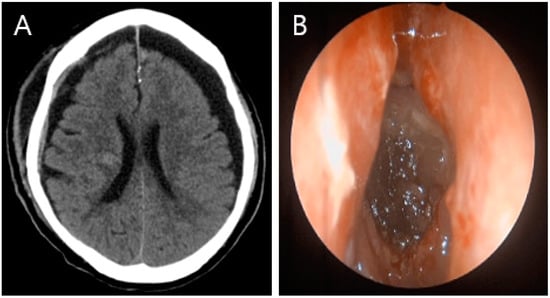

Tension Pneumocephalus Caused by Ethmoidal Roof Fracture: Emergent Surgical Decompression